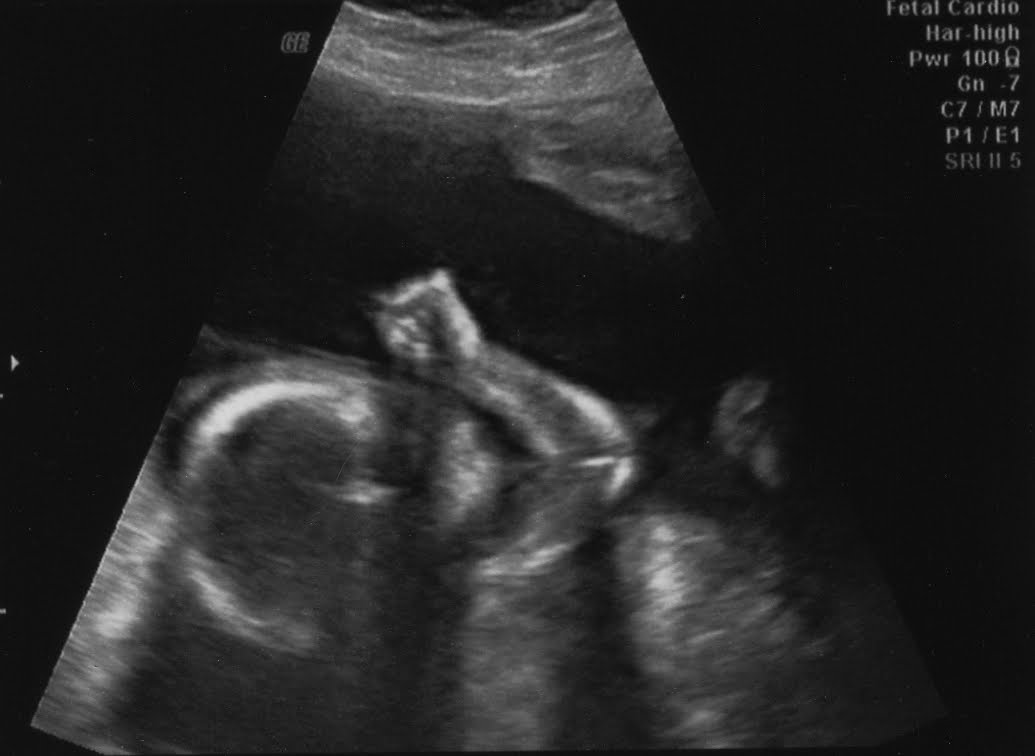

Our latest sonogram

This is our baby boy at 23w5d.

I think he's flipping us off.

But everything looks good otherwise. Yay.